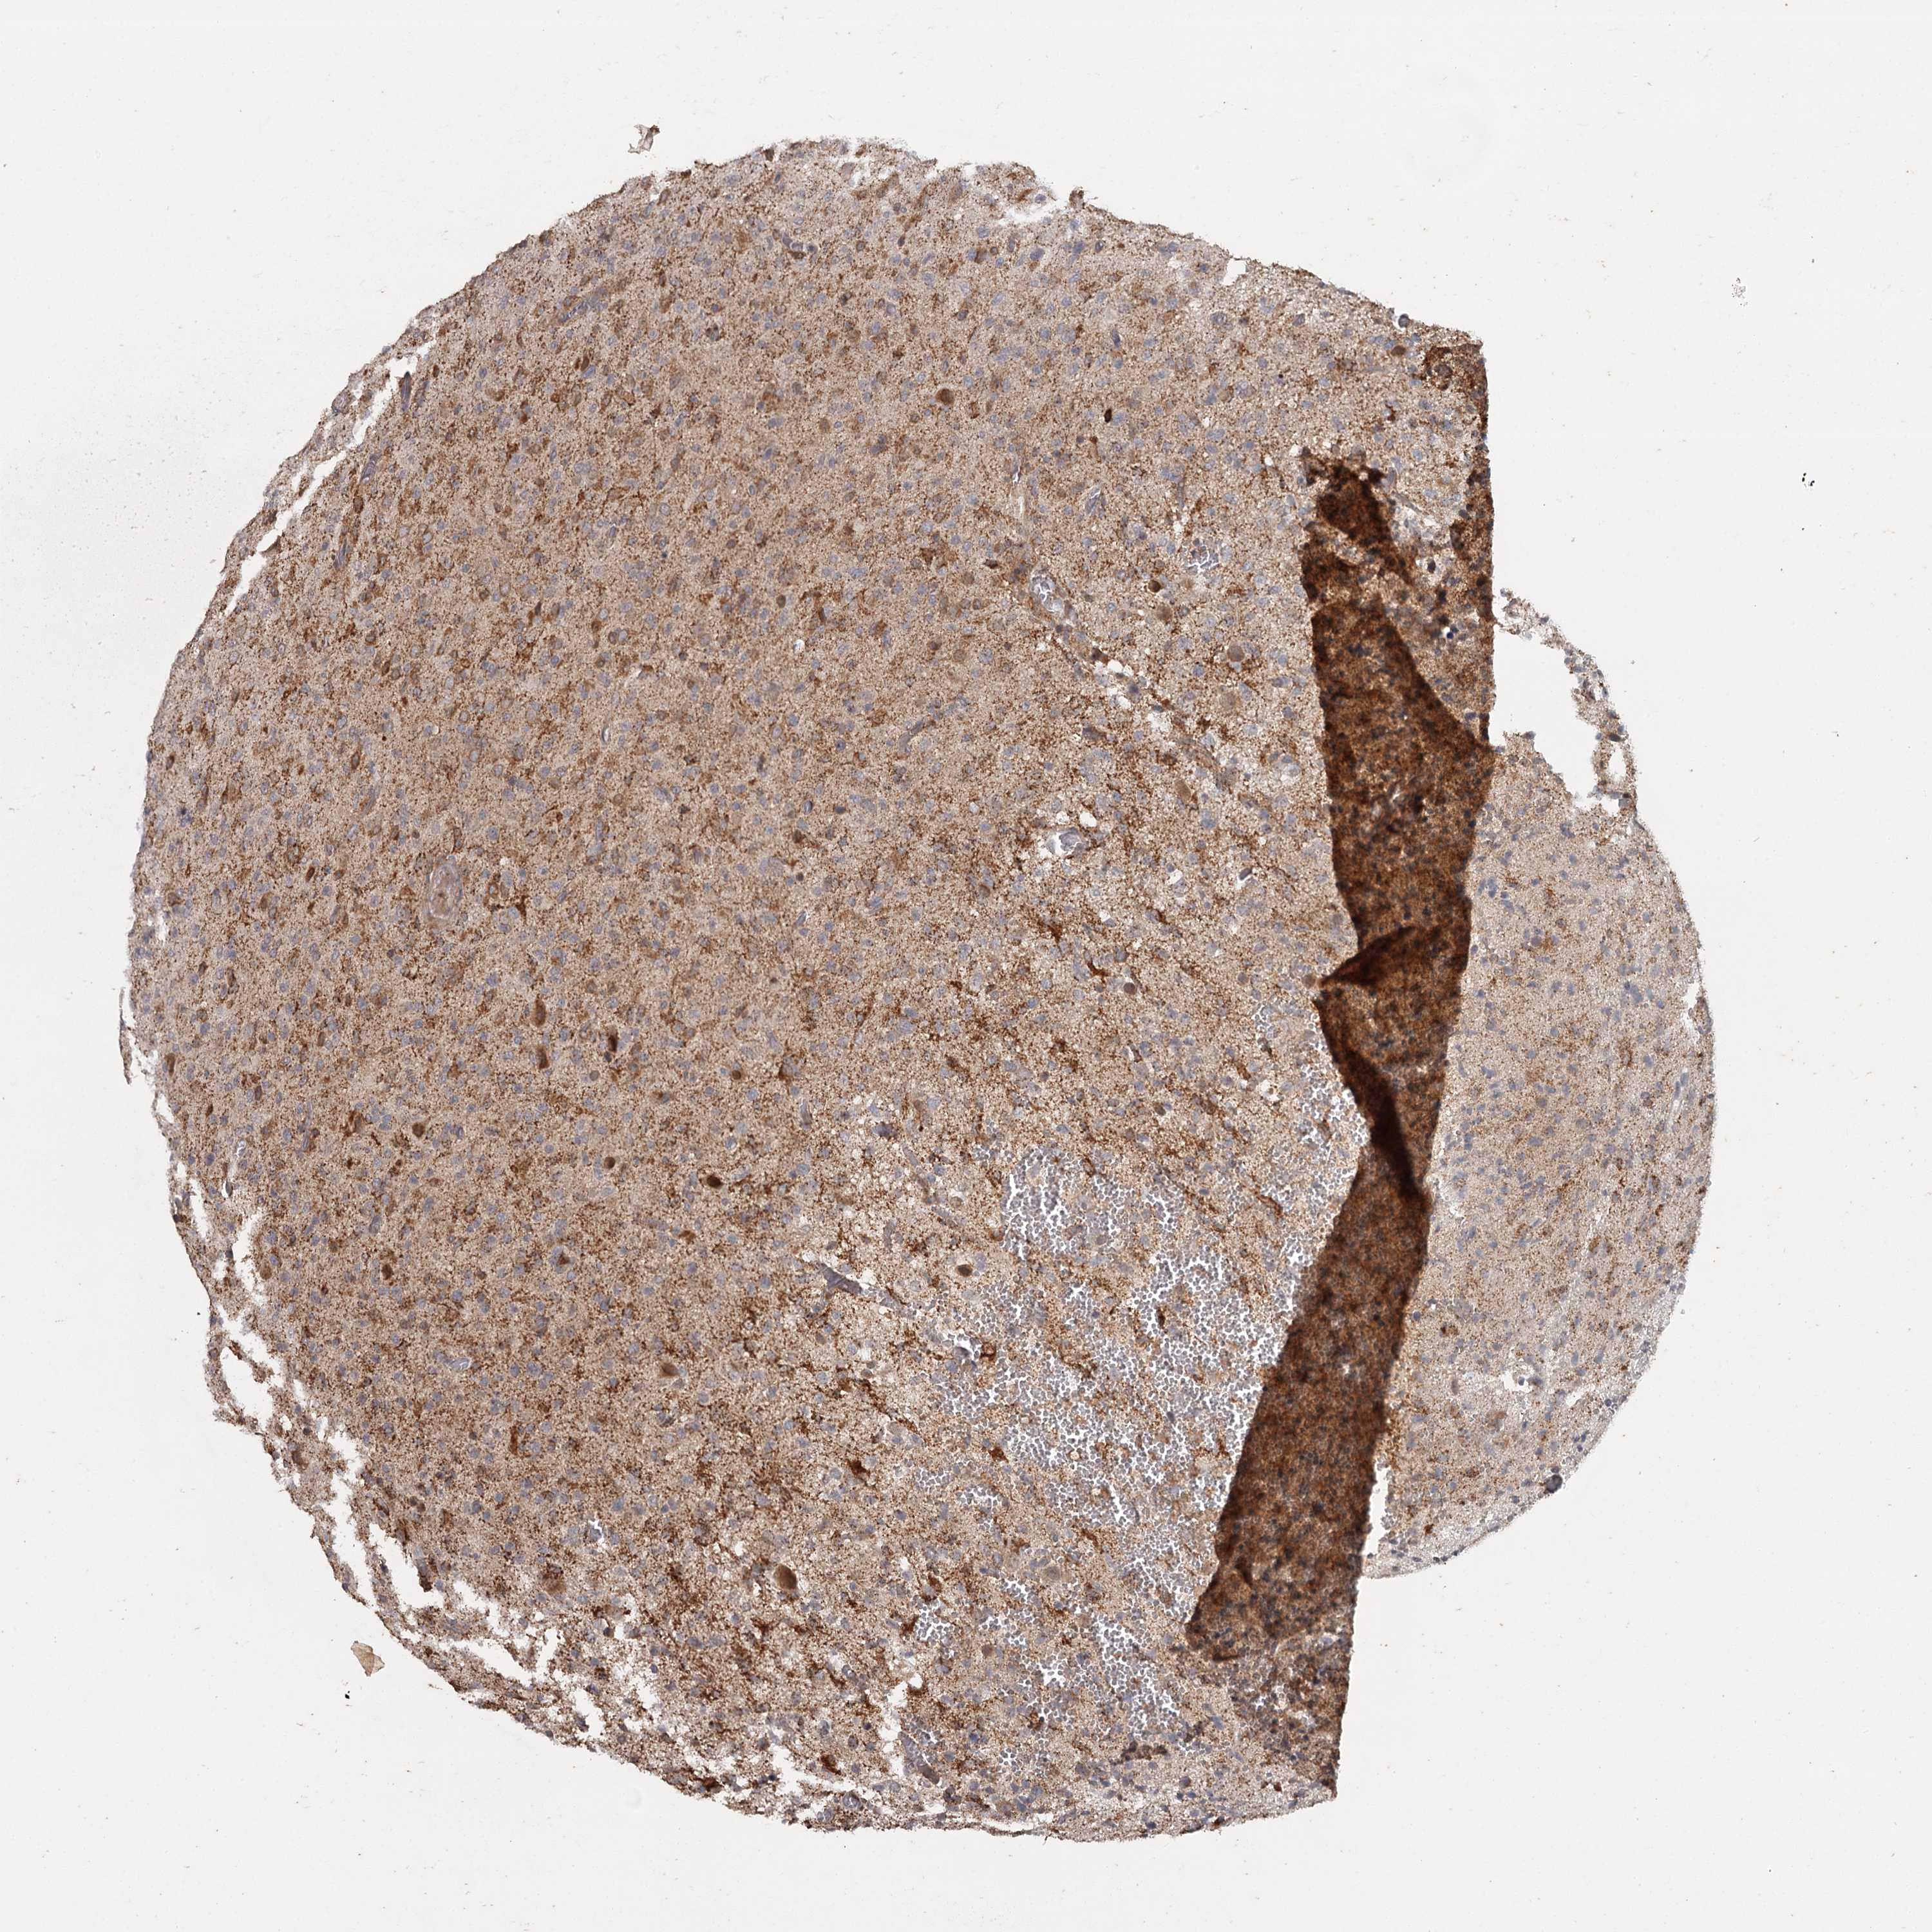

GLIOMA - Protein expressioni

A mouse-over function shows sample information and annotation data. Click on an image to view it in a full screen mode. Samples can be filtered based on level of antibody staining by selecting one or several of the following categories: high, medium, low and not detected. The assay and annotation is described here.

Note that samples used for immunohistochemistry by the Human Protein Atlas do not correspond to samples in the TCGA dataset.

Antibody stainingi

Antibody staining in the annotated cell types in the current human tissue is reported as not detected, low, medium, or high, based on conventional immunohistochemistry profiling in selected tissues. This score is based on the combination of the staining intensity and fraction of stained cells.

Each image is clickable and will lead to virtual microscopy that enables deeper exploration of all samples and also displays staining intensity scores, fraction scores and subcellular localization as well as patient and tissue information for each sample.

Antibody HPA039106

Staining

High

Medium

Low

Not detected

Intensity

Strong

Moderate

Weak

Negative

Quantity

>75%

75%-25%

<25%

None

Location

Nuclear

Cytoplasmic/membranous

Cytoplasmic/membranous,nuclear

Glioma, malignant, High grade

Glioma, malignant, Low grade

Glioblastoma, NOS